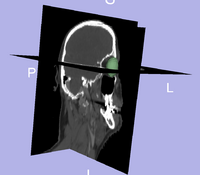

Initial experiments show that bony structures such as the mandible can be segmented accurately with a variational active contour. However, for soft tissue such as the brain stem, the intensity profile does not contain sufficient information for reasonably accurate segmentation. To deal with "soft boundaries" infinite dimensional active contours must be constrained by using shape priors and/or interactive user input. One way to constrain a segmentation is shown in our work in MTNS; there, known spatial relationships between structures is exploited. First, a structure we are confident in will be segmented. Using probabilistic PCA a metric used to describe how likely the structure whose segmentation we have obtained is; this metric is essentially a description of how confident we are in the correct segmentation. Then, the location of this structure will be used as prior information(it becomes a landmark) to segment a more difficult structure. Iteratively, the nth structure to be segmented will have n-1 priors do draw information from with a confidence metric for each prior. The likely location of the nth structure, calculated as described above, will serve as an input to constrain an active contours algorithm. Additionally, we have had excellent results when constraining structures of the eye to simple geometrical shapes such as ellipses and tubular to limit the number of free parameter. A sample segmentation of the eye ball is shown below.

Segmentation of the eye ball.